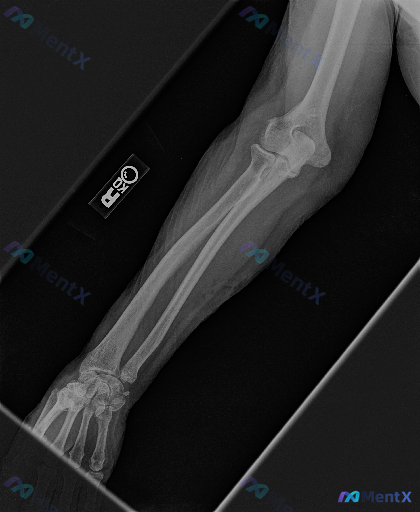

整理到一张放射影像资料,是右侧前臂X光片(正位)。 想请大家先读片,看看这张片子里有没有明确的异常?如果有,你认为最核心、最需要优先关注的是哪一组表现? (注:背景信息暂时先不放,就单看这张影像的表现来讨论)

整理到一份右侧前臂X光正位影像的病例资料,先和大家同步目前可见的表现: 1. 骨骼方面:桡骨远端干骺端区域可见骨皮质中断,远折端有向背侧/桡侧移位的迹象;尺骨茎突处也有骨皮质不连续的表现。 2. 关节方面:桡腕关节的正常解剖关系似乎有改变,下尺桡关节区域看起来间隙不太规整。 3. 软组织:桡骨远端周...